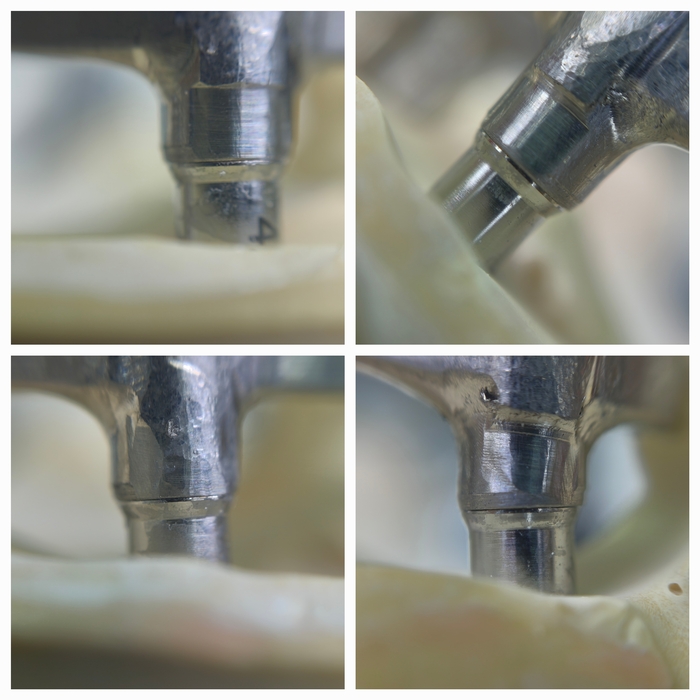

Следующий этап нанесения опакового (непрозрачного) слоя. Он выполняет двойную функцию: маскирует серость титана и является связкой металл–акрил.

С восковой постановки зубов снимается "ключ" с помощью которого зубы переносятся на каркас.

Далее проверяю если не нарушилось положение зубов при переносе, моделирую форму десны будущих протезов, снимаю при помощи технического силикона формы в которые заливается пластмасса.